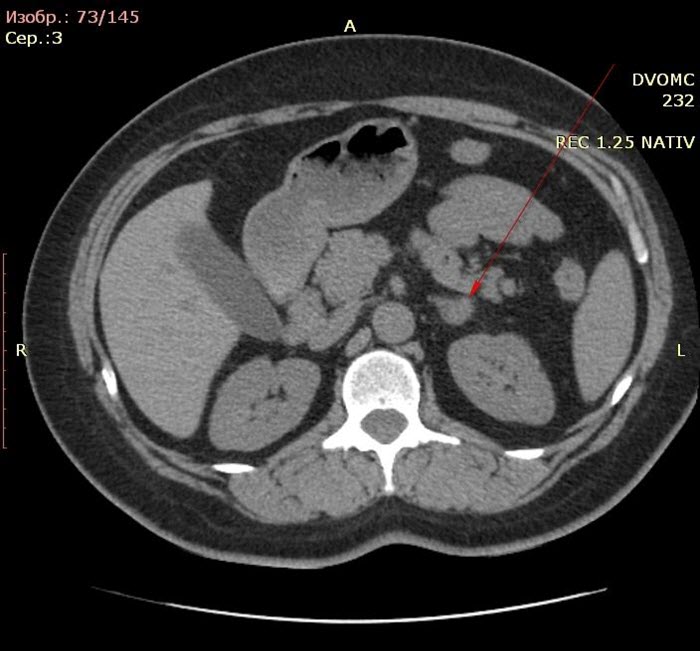

- Магниторезонансная или компьютерная томография гипофиза и надпочечников, контрастная визуализация надпочечников – позволяют сделать вывод о природе синдрома.

Кроме исследований, направленных непосредственно на поиск причины заболевания, проводятся также другие, преследующие цель определить тяжесть осложнений. Рентгенография и компьютерная томография дают информацию об изменениях, произошедших в костной ткани в результате течения болезни. Анализы крови позволяют выявить такое осложнение, как диабет.

Хирургические методы уместны при диагностированной болезни Иценко-Кушинга, при наличии доброкачественных и злокачественных опухолей, локализующихся также в надпочечниках или других внутренних органах. Удаление новообразования эффективно решает проблему повышенной продукции гормонов. Параллельно могут быть назначены облучение и лекарственная терапия.